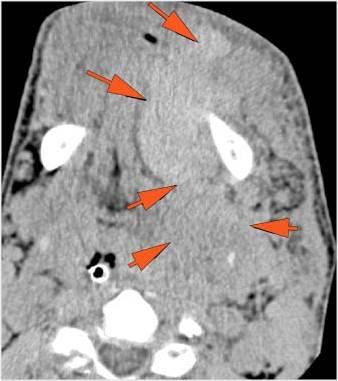

Facial and Scalp Soft Tissues and Airway